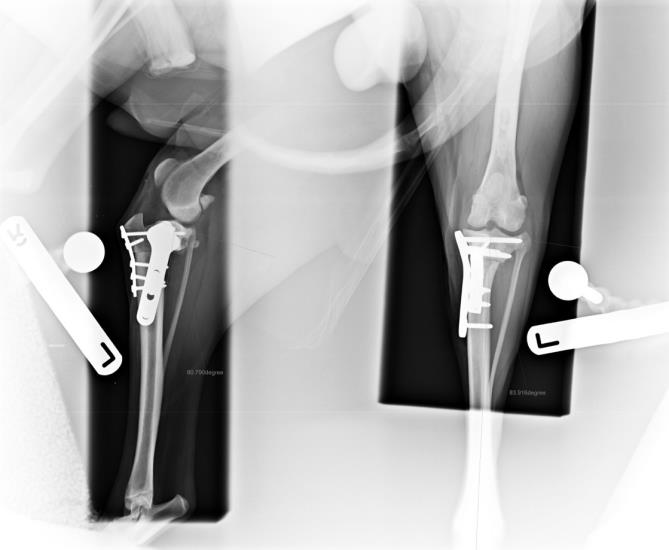

- Concomitant medial patellar luxation (Figure 4)

- Extreme tibial plateau angle (Figure 5)

Figure 4. Staged bilateral surgical correction of combined distal femoral varus, grade ¾ medial patellar luxation and cranial cruciate ligament rupture using distal femoral ostectomy, block recession trochleoplasty and transposed tibial plateau levelling osteotomy

Figure 5. Treatment of combined excessive tibial plateal angle (56 degrees) and severe tibial valgus deformity using a combined TPLO and cranial and medial closing wedge ostectomies